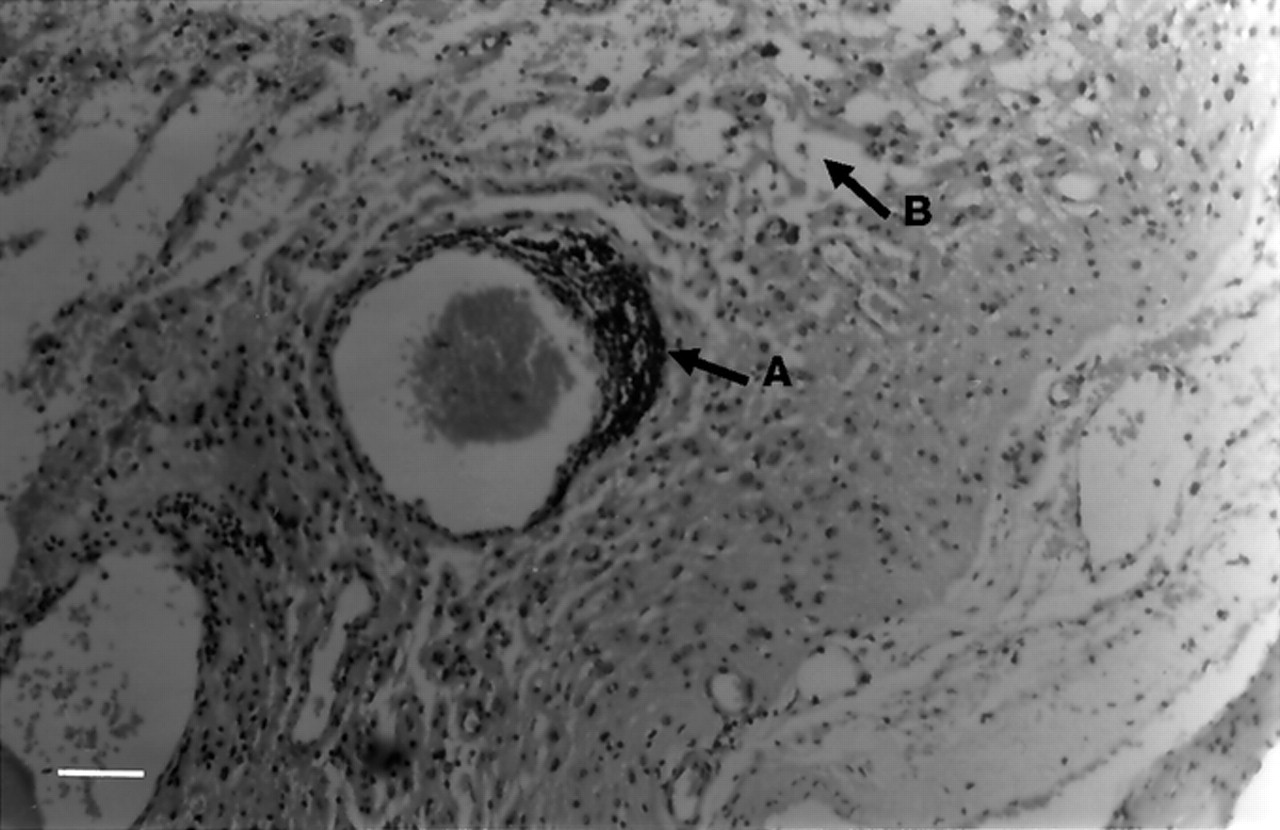

1990年增加T2信号正确的中央沟在大脑核磁共振。在corticectomy,活检标本显示典型的再保险变化(图1)。组织学、原位杂交和PCR切除大脑的单纯疱疹病毒(HSV)、巨细胞病毒(CMV)弓形虫是负的。

图1所示。额叶皮质活检标本从病人1。(一)淋巴细胞性血管周的成套。(B)空泡的改变引起皮质结构的崩溃。他走时污渍。酒吧= 6.6μm规模。在更高权力的外表显示进一步变化的典型Rasmussen的脑炎,与含有淋巴细胞的炎性浸润,巨噬细胞,小胶质细胞反应性星形胶质细胞和神经元变性的不同阶段(没有显示)。